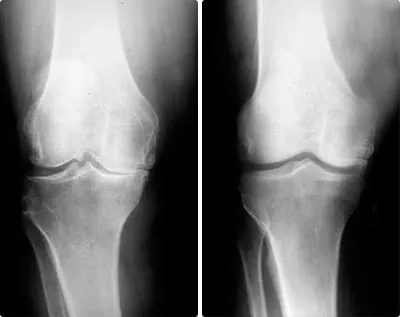

9.22% Sportivii sunt cei mai frecvenți clienți ai sălilor de recuperare fizică terapeutică și de fizioterapie. Ei prezintă leziuni cu diferite grade de severitate care pot fi împărțite în două grupuri: leziuni musculare și leziuni articulare. Rupturi, întinderi, artroză cronică. Nu poți evita riscurile dacă nu te protejezi la timp.